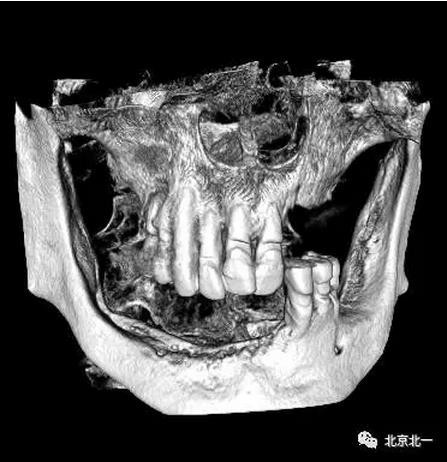

80歲,上頜骨量高度和寬度可, 計(jì)劃即刻拔牙+ALL ON 6

下頜已經(jīng)ALL04